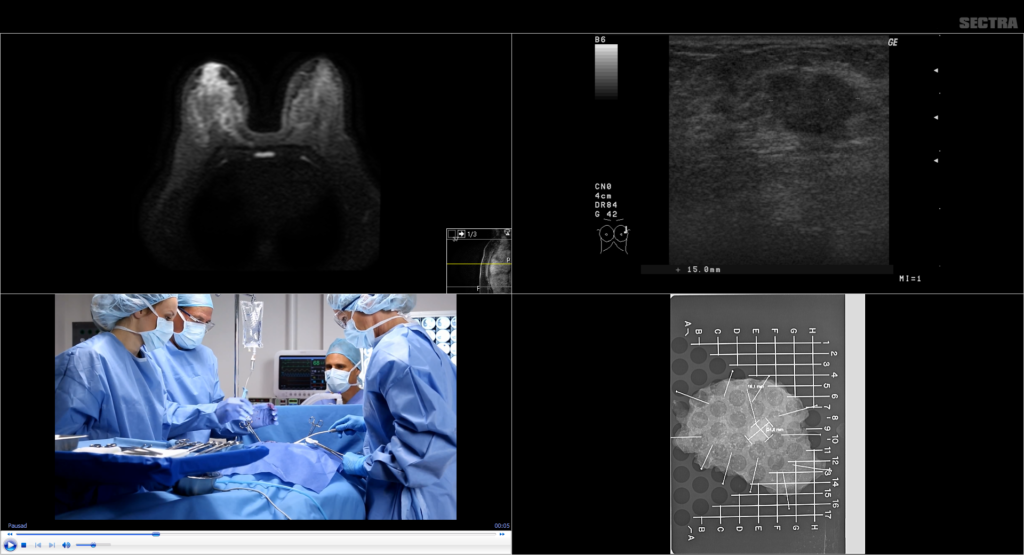

Sectra Breast Imaging PACS is a comprehensive, vendor-neutral, breast imaging solution supporting both high-volume screening, advanced diagnostic workflows as well as telemammography services. It gives you a full patient overview by allowing you to read all types of radiology images such as mammograms, MRI, and tomosynthesis—all from a single workstation. It is a scalable solution that lets you grow without limits on the same platform. Specializing in breast imaging PACS for almost 20 years, Sectra has an installed base that includes some of the world’s largest and most prominent breast imaging centers. Sectra’s KLAS-awarded PACS is praised by users around the world for its ease of use, rock-solid nature, and versatility in allowing radiologists to perform the vast majority of their workload from a single application.

With the ability to store and display all breast imaging objects—including mammograms, ultrasounds, MRI, and digital breast tomosynthesis—from any vendor, Sectra Breast Imaging PACS efficiently supports your diagnostic workflow.

In Sectra’s diagnostic application, you have instant access to all the tools you need for both reviewing studies and reporting—including CAD support, implant masking, and desktop integration with clinical applications for advanced breast MRI tools. Thanks to native reporting tools or tight integration with any of the major mammography reporting providers such as MagView, Penrad, MRS, Epic Radiant and Ikonopedia, the reporting is also done in the same application—close to the images.